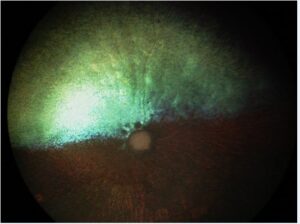

Progressive Rod-Cone Degeneration (PRCD) is a form of Progressive Retinal Atrophy (PRA) in which the cells in the dog’s retina degenerate and die. PRCD-PRA for dogs is similar to retinitis pigmentosa in humans. Most affected dogs will not show signs of vision loss until 3-5 years of age. Complete blindness can occur in older dogs.

The retina is a membrane located in the back of the eye that contains two types of photoreceptor cells. These cells take light coming into the eyes and relay it back to the brain as electrical impulses. These impulses are interpreted by the brain to create images. In dogs suffering from PRCD or PRA, the photoreceptors begin to degenerate, causing an inability to interpret changes in light. This results in a loss of vision. Rod cells, which normally function in low-light or nighttime conditions, begin to degenerate first. This leads to night-blindness. The cone cells, which normally function in bright-light or daytime conditions, will deteriorate next. Over time this can lead to complete blindness.

In addition to the PRCD-PRA mentioned above, two mutations have been identified specifically in Golden Retrievers. They are known as PRA1 and PRA2. Progressive Retinal Atrophy (PRA) is a category of genetic mutations that cause vision loss and blindness. Photoreceptor cells in the retina begin to degenerate, typically progressing from a loss of night vision to complete blindness. PRA affects many different dog breeds, and these two mutations are breed-specific.

Both PRA1 and PRA2 are inherited in an autosomal recessive manner. This means that a dog must inherit a copy of the mutation from each parent to be affected by the disorder. Dogs with one copy of the mutation will not show any signs or symptoms of PRA, however, they can still pass on that mutation to any offspring.